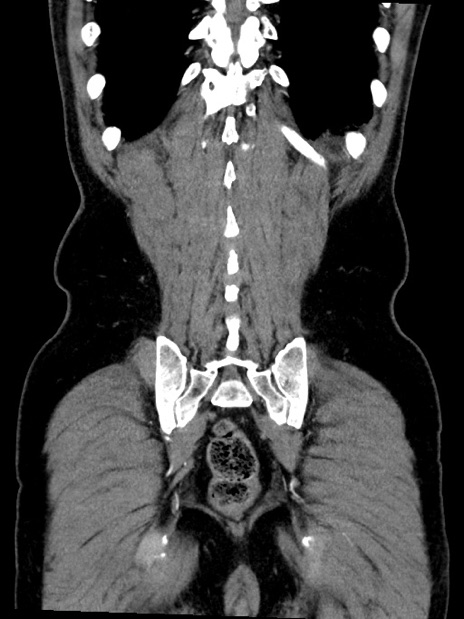

症例35(冠状断像)

【症例】70歳代 男性

【主訴】腹部膨満、嘔吐

【現病歴】昨日より腹部膨満感出現。本日増悪し、仙痛出現。嘔吐あり、受診。

【既往歴】糖尿病、胆摘後

【身体所見】BP 149/80mmHg、HR 74/min、BT 35.9℃、腹部:膨満、軟、圧痛なし。腸雑音減弱あり。上腹部正中切開瘢痕あり。

【データ】WBC 13500、CRP 1.72

横断像